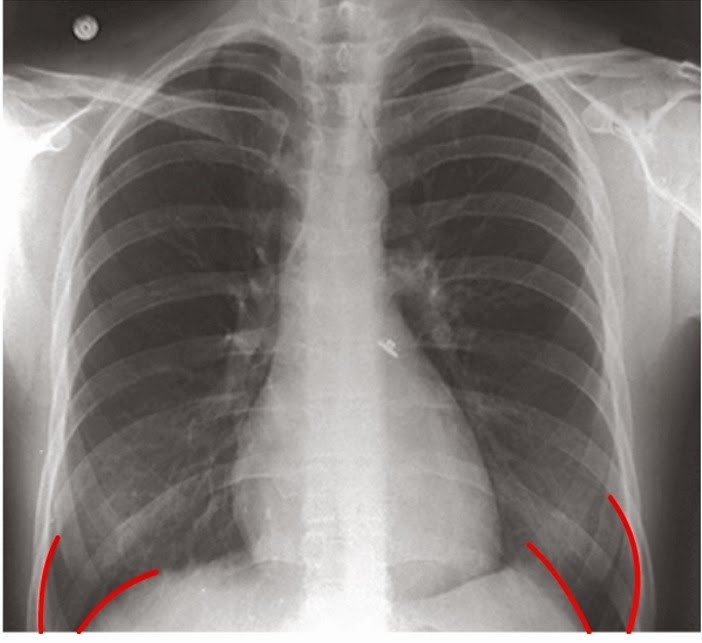

WebThis website uses cookies to improve your experience while you navigate through the website. Out of these cookies, the cookies that are categorized as necessary are stored. WebSe observan ambos senos costofrénicos libres y ausencia de signos de neumotórax. B) Radiografía realizada al tercer día de ingreso. Se observa cómo el ángulo costofrénico. Websenos costofrénicos. Inglés. costophrenic angle. Última actualización: 2012-07-25 Frecuencia de uso: 1 Calidad: Referencia: Wikipedia. Español. sen. Inglés. senna. Última.

WebA continuación, puedes ver ver un listado de opiniones sobre senos costofrenicos libres y opinar sobre este tema. Aquí podrás encontrar opiniones relacionadas con senos. WebAnswers & Comments. Anónimo. Verified answer. Es una parte no visible de tu cuerpo que es necesario ver a la hora de realizar una radiografia pulmonar. Saludos y Paz! WebAl parecer debe decir borramiendo del seno costofrénico, bueno eso significa que la pleura que cubre a tu pulmón derecho presenta un poco de líquido pero es mínimo y que.